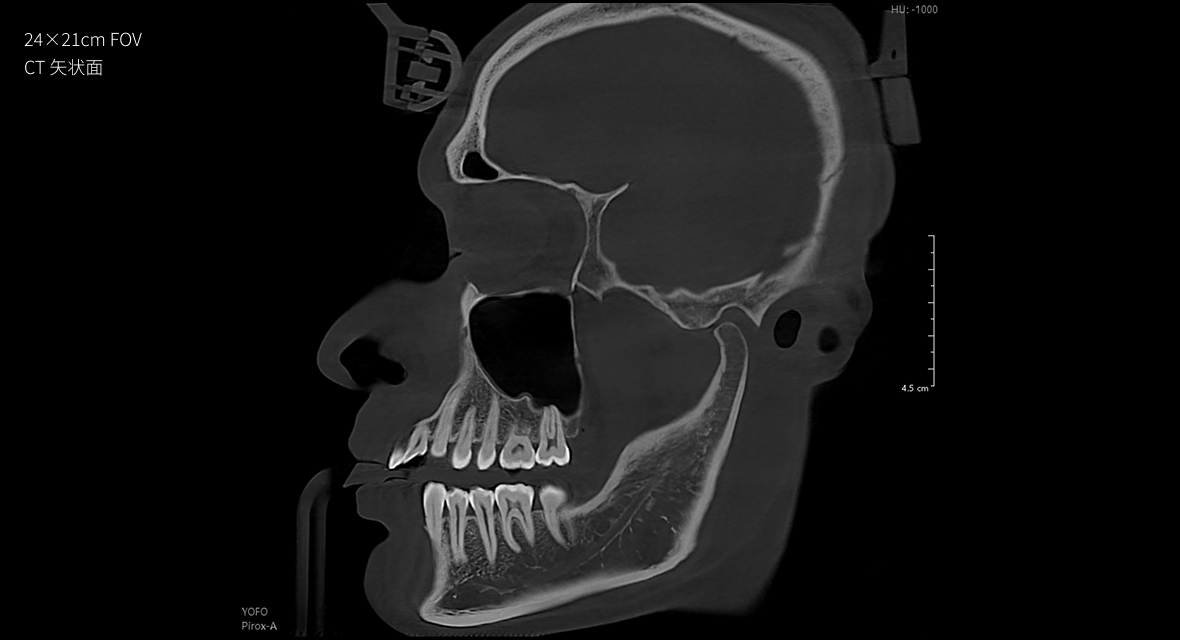

• 超大视野

24×21cm超大视野,口腔颌面一览无余

24×21cm

非拼接超大视野